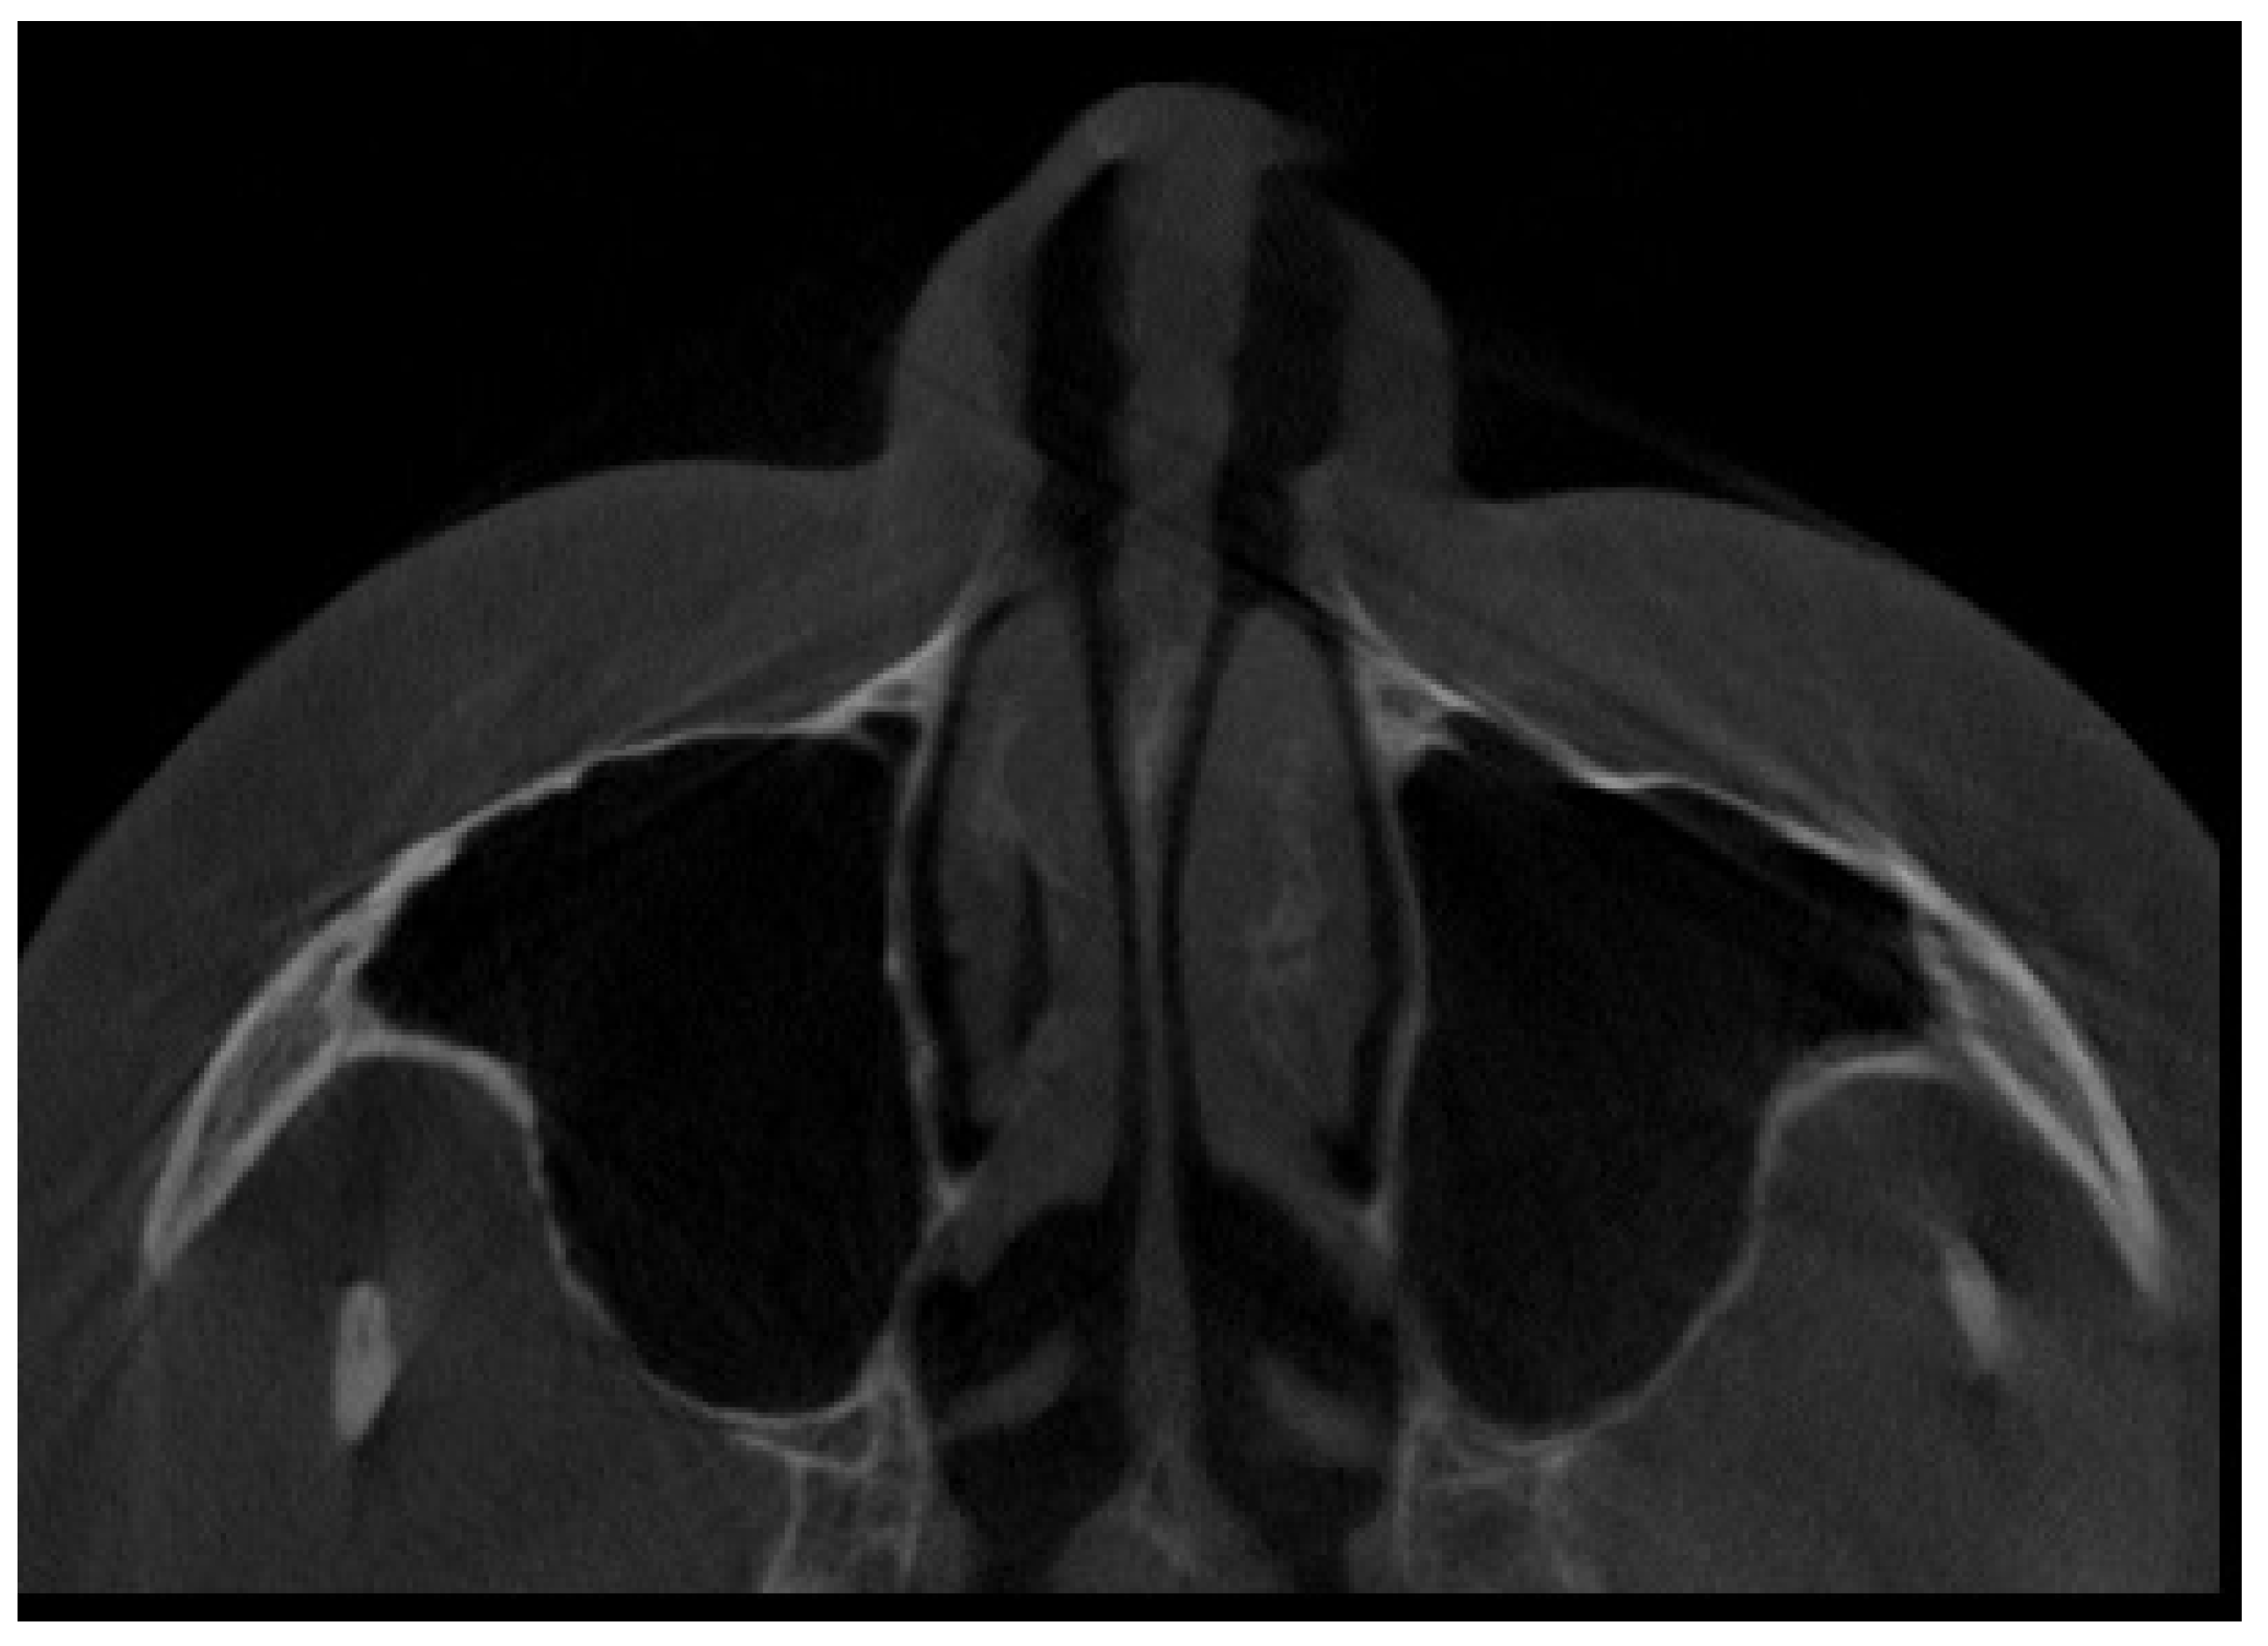

2. Material and Methods

2.2. Cone Beam Computed Tomography Characteristics

2.3. Methods—Classification Proposal